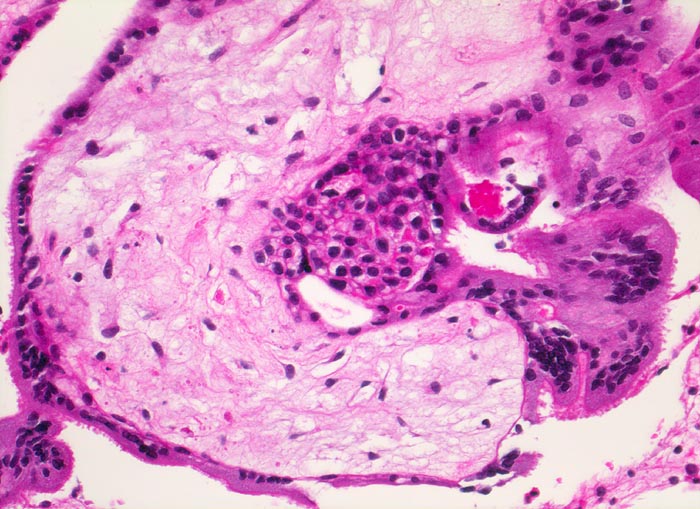

PathoPic – image database / PathoPic ID 4674 - Abortkurettage: choriales Gewebe

Abortkurettage: choriales Gewebe

Gefässe sind im degenerierten Zottenstroma nicht sicher zu erkennen. Die Zotte wird bedeckt von fokal leicht proliferiertem Zytotrophoblast und mehrkernigem Synzytiotrophoblast.

Missed abortion in der 11. Schwangerschaftswoche, sonographisch entsprechend der 9. Schwangerschaftswoche.

Histologie

200